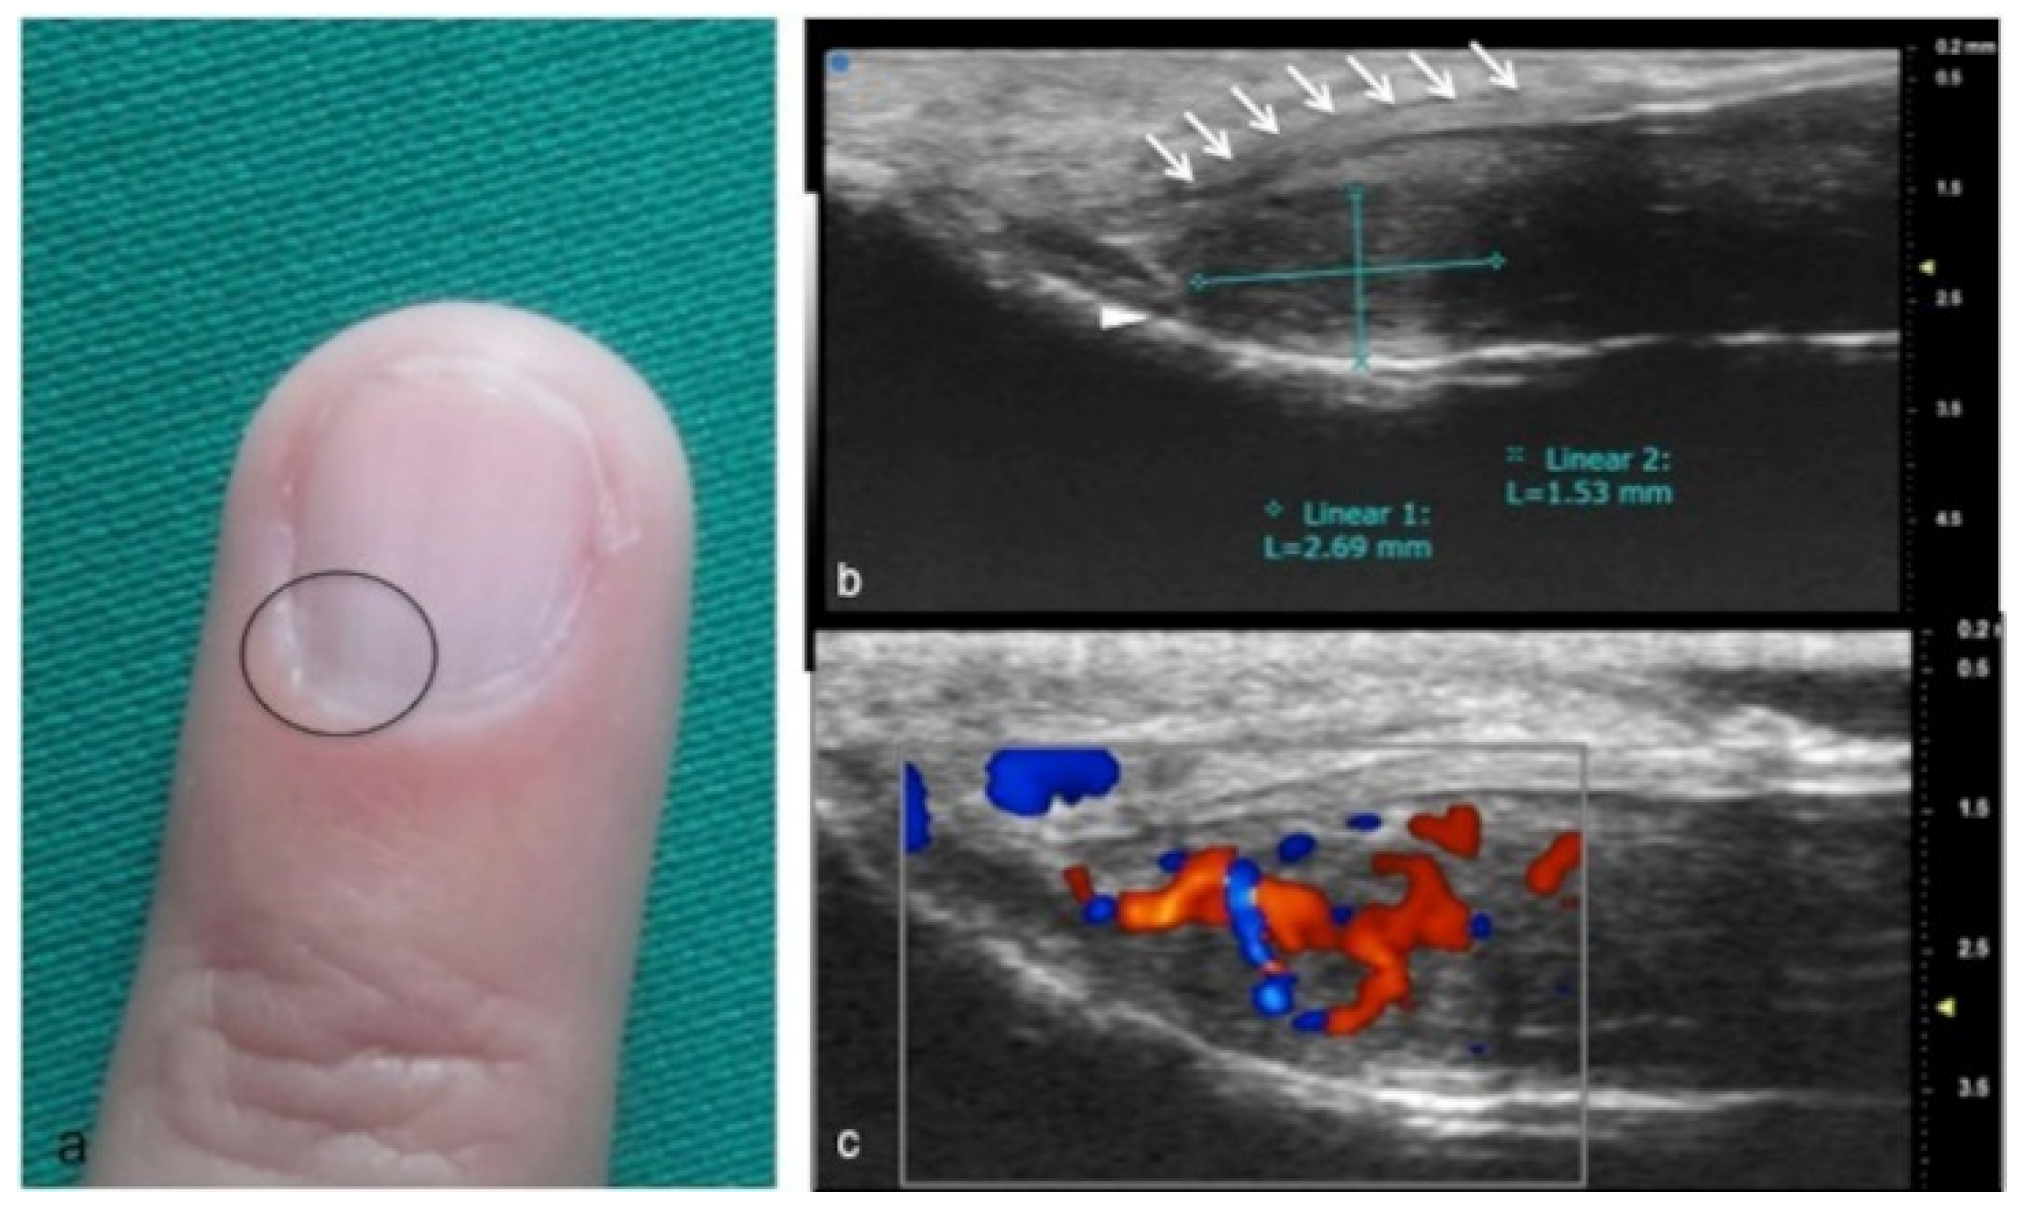

Figure 11.

Glomus tumor. The location corresponds to the pulp of finger IV (a). The patient had the classical triad of symptoms: paroxysmal pain, pinpoint pain, and cold hypersensitivity, lasting for two years. In (b), UHFUS shows a well-delimited nodule in contact with the adjacent phalangeal bone (arrowhead), but no cortical deformity is present. No significant hyperemia on color Doppler was noticed. On CUS (c), the nodule was delineated only thanks to the help of the preliminary UHFUS exam.

Figure 12.

Glomus tumor in the subungual space. No clear alterations were visible during clinical examination at the site of pain (circle in (a)). In (b), UHFUS effectively demonstrates the presence of a hypo-isoechogenic nodule (calibers) in contact with the adjacent phalangeal bone (arrowhead) under the nail plate (arrows). Note the small deformation of the nail plate. Mild vascularization on color Doppler was present (c).